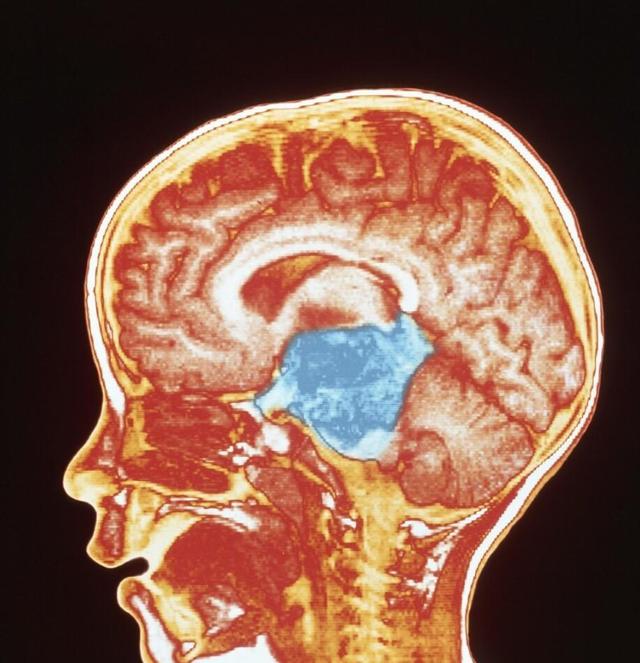

大脑是我们身体最重要的器官,如果怀疑脑袋里长了肿瘤,那么哪些检查能确诊那肿瘤呢?脑部CT检查、脑电图检查、头颅X片等是脑肿瘤常做检查。脑电图检查  脑电图检查是比较重要的,对大脑半球生长快的脑肿瘤具有定位价...【全文】